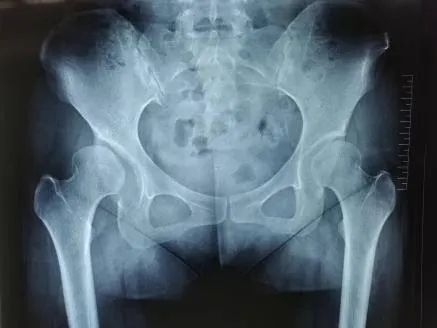

图3-4:术前影像(右侧髋关节发育不良)